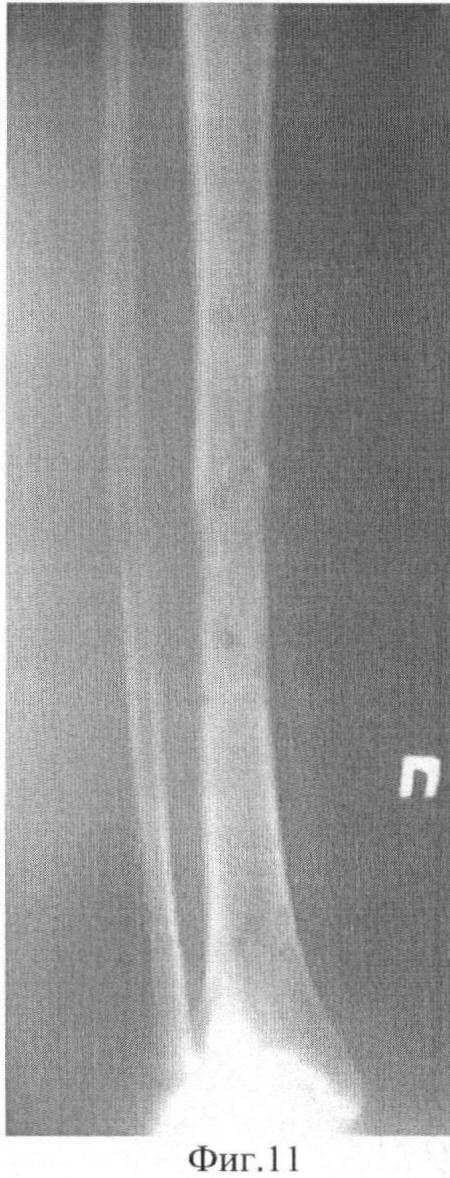

Фиг.11 Фоторентгенограммы больного после снятия аппарата внешней фиксации: прямая проекция;

Демонстрируем сказанное клиническим наблюдением. Больной С-ов, 18 лет, история болезни 12608/2008. В результате ДТП получил оскольчатый перелом средней трети обеих костей правой голени со смещением фрагментов (Фиг.5 и 6). Выполнен чрескостный остеосинтез аппаратом внешней фиксации. Вначале были проведены базовые чрескостные элементы и смонтирована рама аппарата (Фиг.1). Затем смещение фрагментов было устранено с помощью стержней-шурупов (Фиг.2). При этом возникли деформация и напряжение базовых чрескостных элементов. Были введены стабилизирующие стержни-шурупы (Фиг.3). После этого, не опасаясь вторичного смещения фрагментов, базовые чрескостные элементы были переустановлены (Фиг.7 и 8). Период фиксации составил 103 дня. Осложнений (вторичного смещения фрагментов, воспаления мягких тканей в области выхода чрескостных элементов) отмечено не было (Фиг.9 и 10). Через неделю после снятия аппарата внешней фиксации (Фиг.11-14) больной приступил к труду.